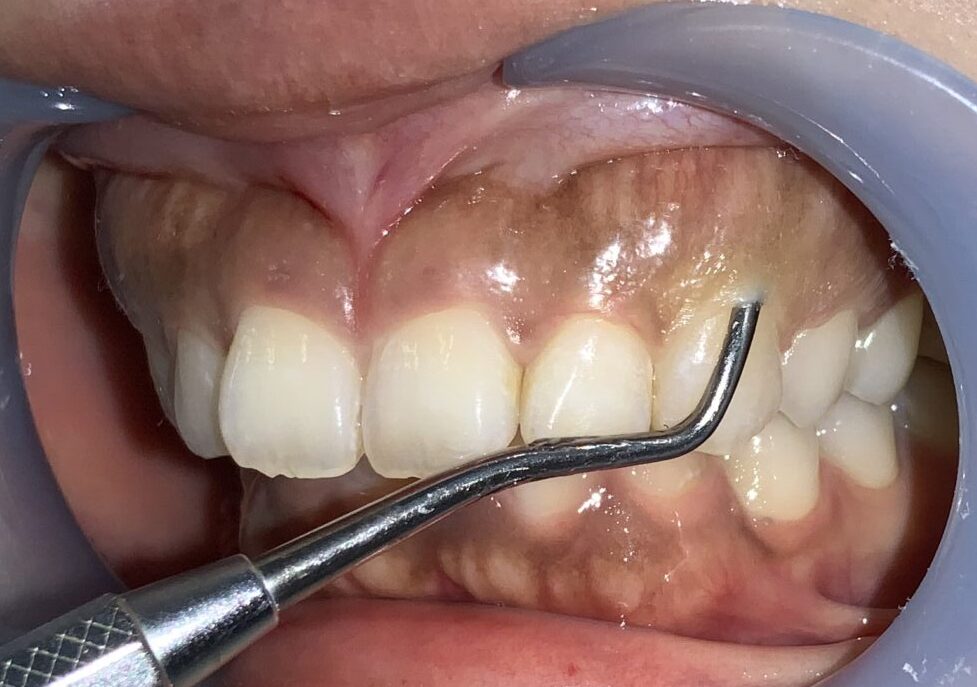

患者様のご希望により、4番目の小臼歯も整形します。費用の追加はありません。

奥歯になりますが、綺麗に整えることが出来ます。

犬歯です。通常は大きく見えるはずなのに、たくさんの歯ぐきが被ってしまっていて、とても小さくなっている犬歯です。

綺麗に整えましょう

最後に4番目の歯。小臼歯です。

奥歯ですが、口角が上がると見えるので、綺麗に整えることが出来ます。